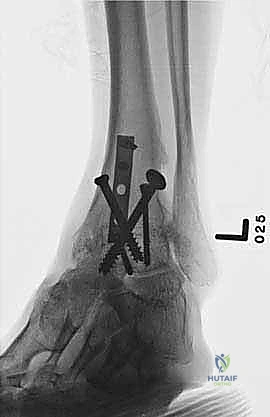

- الأشعة السينية أثناء الوقوف (Weight-bearing X-rays): هي الفحص الذهبي والأهم. يجب أن تؤخذ الأشعة والمريض واقف لتحمل الوزن. تظهر الأشعة تضيق المسافة المفصلية (دليل على فقدان الغضروف)، وجود نتوءات عظمية، تصلب العظم، وأي انحراف في محور المفصل.

- التصوير المقطعي المحوسب (CT Scan): يطلبه الدكتور هطيف لتقييم جودة العظام (Bone stock)، تحديد حجم الأكياس العظمية، ورسم خريطة ثلاثية الأبعاد للتشوهات المعقدة قبل الجراحة.

- التخطيط الجراحي الرقمي: باستخدام صور الأشعة المقطعية، يقوم الدكتور هطيف بتخطيط الجراحة على الكمبيوتر لاختيار حجم المسامير والشرائح المناسبة بدقة مليمترية.